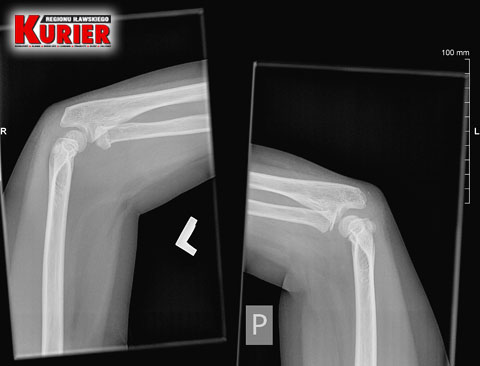

Karolina Wiśniewska zgłosiła się na iławski Szpitalny Oddział Ratunkowy z synem Szymonem, który po niefortunnym upadku skarżył się na ból łokcia. Wykonano prześwietlenie i stwierdzono stłuczenie. Wypisano chłopca do domu z zaleceniem opatrunków. Ręka jednak coraz bardziej puchła. Dzięki czujności matki dziecko ponownie trafiło do szpitala, ale tym razem w Nowym Mieście, gdzie stwierdzono złamanie łokcia z przemieszczeniem, a następnie do olsztyńskiego, w którym podczas operacji ustabilizowano rękę drutem. Poproszony przez nas o komentarz rzecznik iławskiego szpitala Tomasz Więcek milczy... od ponad 2 miesięcy.

– Tu pan doktor w odróżnieniu do lekarki w Iławie zlecił wykonanie prześwietlenia jednej i drugiej ręki, dla porównania – opowiada pani Karolina. – Gdy tylko zobaczył zdjęcie, od razu stwierdził złamanie łokcia z przemieszczeniem. Nie było już pytania, czy dziecko chce mieć założoną szynę czy nie. Od razu to zrobiono i skierowano nas do Olsztyna.

– Pytałam tam doktora, czy na zdjęciu z prześwietlenia w Iławie widać złamanie – mówi kobieta. – Oczywiście potwierdził i pokazał mi nawet, gdzie dokładnie do niego doszło. Konieczna była prawie godzinna operacja, podczas której ustabilizowano rękę drutem. Przeprowadzono ją od razu, bo lekarz mówił, że każda minuta w tym stanie jest na niekorzyść dziecka.

W nowomiejskim szpitalu od razu rozpoznano

złamanie łokcia z przemieszczeniem

W olsztyńskim szpitalu podczas operacji

ustabilizowano rękę chłopca drutem

W nowomiejskim szpitalu dla porównania

wykonano prześwietlenie obu rąk i stwierdzono

w lewej złamanie łokcia z przemieszczeniem